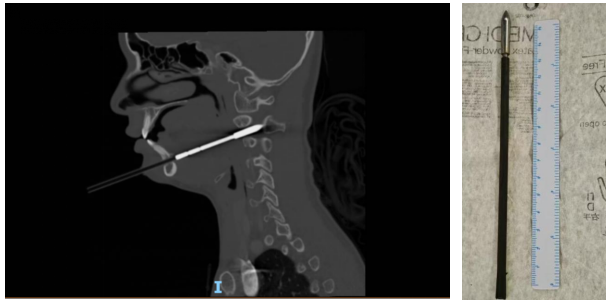

6月2日凌晨,娜娜在父母和教练的陪伴下,紧急抵达北京儿童医院急诊。首诊的急诊内科戴国瑞医师迅速对娜娜的病情进行了全面评估。尽管娜娜的生命体征平稳、神志清楚,肢体活动和感觉也未见异常,但CT影像结果却揭示伤情的复杂性:箭矢穿通了下颌骨和右侧颈2椎体,累及椎管,横突孔内缘骨质可疑受累,且箭头尖段进入椎管长度约12毫米,右侧咽旁间隙受累,局部气道向左侧偏移。

6月2日凌晨2时,娜娜被送入手术室。经验丰富的麻醉科医生在颈部制动、张口受限的复杂情况下,成功完成了气管插管,为这场牵动人心的手术奠定了良好基础。麻醉完成后,耳鼻咽喉头颈外科副主任医师刘悄吟对娜娜的口咽部进行了术前探查,发现多发淤青、水肿和软组织陈旧出血。随后,骨科副主任曹隽主任医师和口腔科副主任医师陈卓合力进行异物拔除。他们首先稳定患儿头部,用大力钳夹住箭杆末端,缓慢拔出。起初阻力较小,但箭头退至下颌骨部位时,阻力明显增加。两位医生凭借精湛的技艺和沉着冷静的心态,在确保患儿生命体征平稳的前提下,加大了拔出力量。最终,深深扎在下颌骨里的箭矢被完整取出!术后再次用喉镜探查,确认无活动性出血。